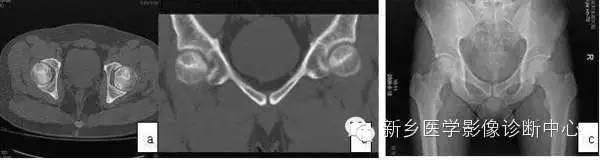

MRI出现阳性改变到CT扫描清楚显示病灶的间隔多数患者为6月~1年。CT可清楚显示Ⅱ期ONFH病灶,典型的改变为硬化带包绕坏死灶,部分ONFH的坏死灶内显示斑点状或片状骨化(图2)。Ⅲ期ONFH的CT扫描可显示股骨头病灶皮质骨断裂(冠状位、矢状位、或轴位重建)。因此,CT扫描对清楚显示病灶范围、部位、修复情况及鉴别Ⅱ、Ⅲ期有重要作用。

X线片的阳性改变较CT扫描还要延迟,多数病例X线片出现阳性改变在MRI确诊后的1年,少数患者可晚到2~3年,而且X线片的病灶显示均不清楚。因此,普通X线片对Ⅰ、Ⅱ期ONFH的诊断价值有限。但蛙式位X线片对显示新月征有其特殊价值。

图2 CT显示坏死灶明显,硬化带形成(a,b);X线片坏死灶显示不清(c)